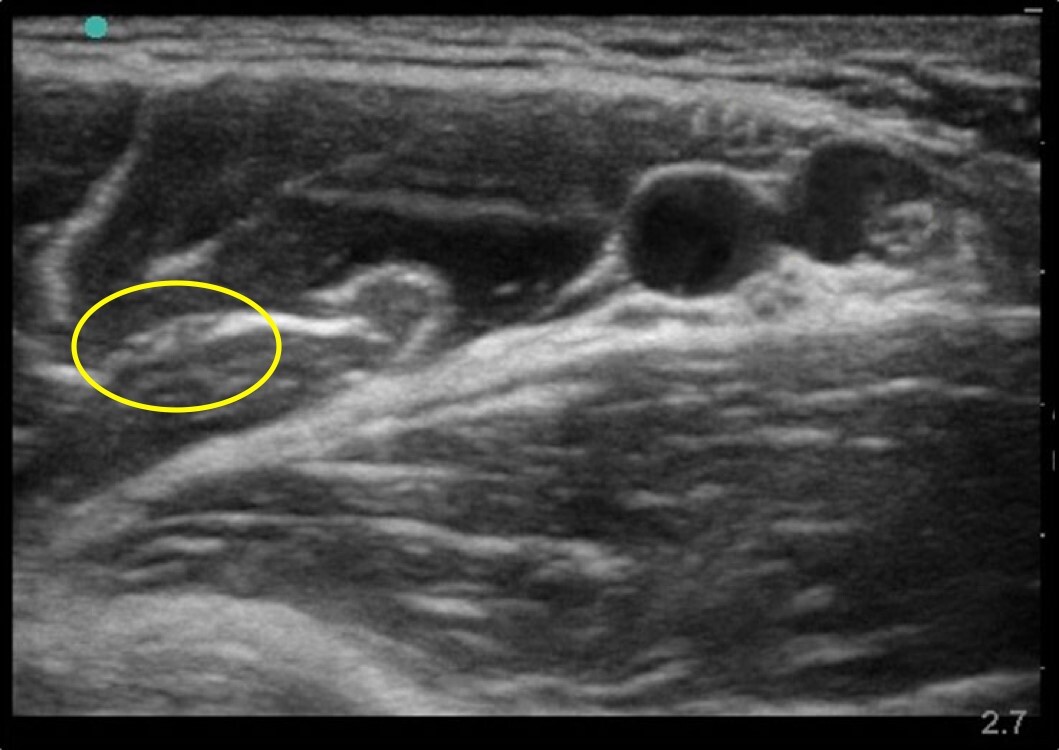

Musculocutaneous Nerve Anatomy Image